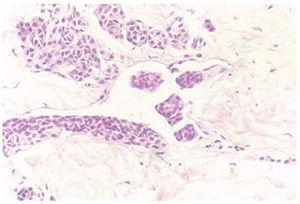

De los 8 pacientes estudiados, siete eran mujeres. La edad media fue de 26 años. Macroscópicamente las lesiones pigmentadas presentaron un diámetro medio de 0,4 cm, con contornos regulares y no se apreció discromasia en ninguno de ellos. En los casos 1, 2, 3, 4 y 7 (tabla 1) los pacientes refirieron que la lesión cutánea pigmentada estaba presente desde el nacimiento y/o primera infancia. Histológicamente estos 5 casos cumplían los requisitos de nevo congénitos2,6. Dos de ellos fueron intradérmicos (casos 1 y 4) y tres compuestos (casos 2, 3 y 7). En estos 5 casos se observó, en la dermis reticular, en el seno de la población melanocítica, la presencia de estructuras vasculares linfáticas que contenían en su luz celularidad de hábito melanocítico que adoptaban un patrón arquitectural de masas polipoides (fig. 1) con un revestimiento endotelial de la superficie interna. En el caso número 4 este revestimiento endotelial era parcial, dando la apariencia de que las células melanocíticas del propio nevo empujaban y en algún área sustituían o lesionaban el revestimiento endotelial (fig. 2). En el caso 1 existían además estructuras vasculares linfáticas distantes a la lesión con melanocitos en su luz en forma de agregados irregulares (fig. 3).

Fig. 1.--Crecimiento polipoide intravascular en el seno de un nevo congénito. (Hematoxilina-eosina, ×40.)